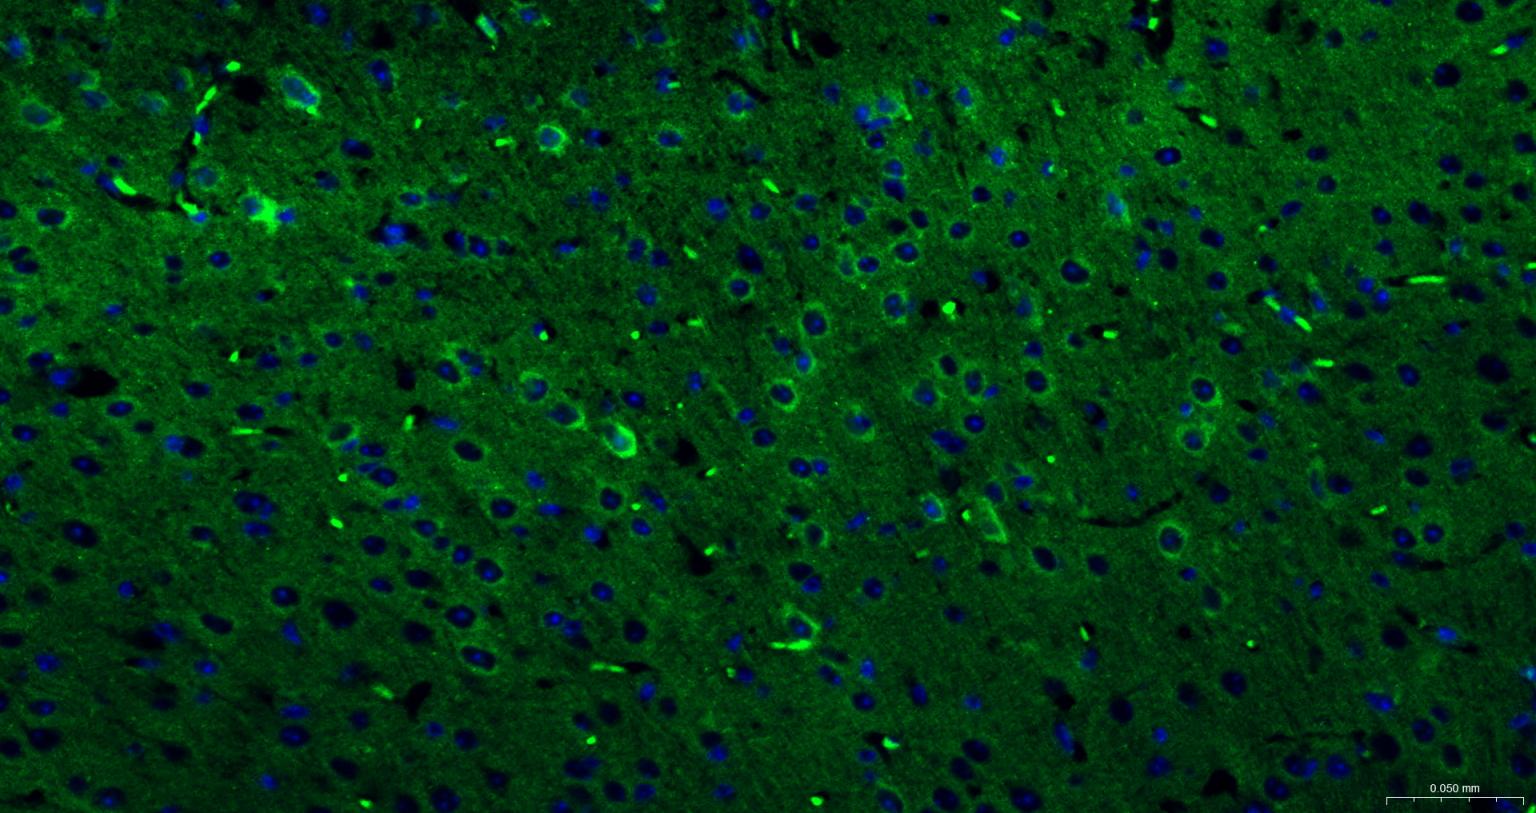

Paraformaldehyde-fixed, paraffin embedded Mouse Cerebrum; Antigen retrieval by boiling in sodium citrate buffer (pH6.0) for 15 min; The section was incubated with DNM1L Polyclonal Antibody, Unconjugated (bs-34001R) at 1:200 overnight at 4°C. Followed by conjugated Goat Anti-Rabbit IgG antibody (Green, bs-0295G-BF488), DAPI (blue, C02-04002) was used to stain the cell nuclei.

Paraformaldehyde-fixed, paraffin embedded Rat Cerebrum; Antigen retrieval by boiling in sodium citrate buffer (pH6.0) for 15 min; The section was incubated with DNM1L Polyclonal Antibody, Unconjugated (bs-34001R) at 1:200 overnight at 4°C. Followed by conjugated Goat Anti-Rabbit IgG antibody (Green, bs-0295G-BF488), DAPI (blue, C02-04002) was used to stain the cell nuclei.